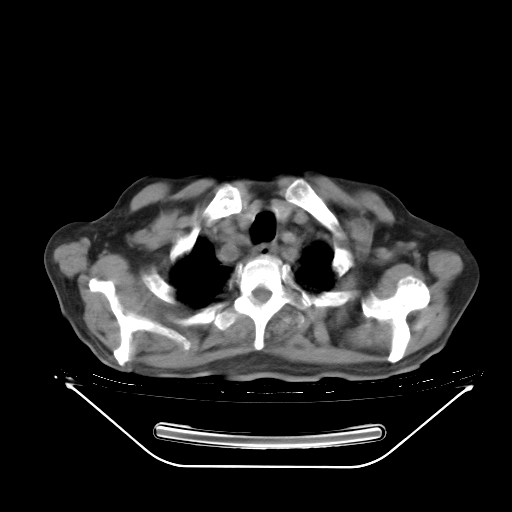

今天复查肺部CT,发现双肺广泛磨玻璃样改变。所以我把3月19日和5月9日相隔50天的肺部CT上传。请大家会诊。

5月9日肺部CT(在4月27日齐鲁医院肺部CT描述部分肺组织磨玻璃样改变,12天后肺组织广泛磨玻璃样改变)

2009年5月9日肺部CT

大致读了系列胸部CT:纵隔窗无明显异常,肺窗:从4、27至今:主要是双肺中下野外带可见毛玻璃样改变,目前处于急性肺泡炎阶段,至于原因考虑1、结替组织或胶原血管性疾病所致?2、恶性疾病如恶组在肺部所致的表现或细支气管肺泡癌?3、药物或其它原因如肺蛋白沉着症所致肺泡炎目前不太可能?总之,明天就去请我院的呼吸科、感染科、血液科和临免专家会诊哈。